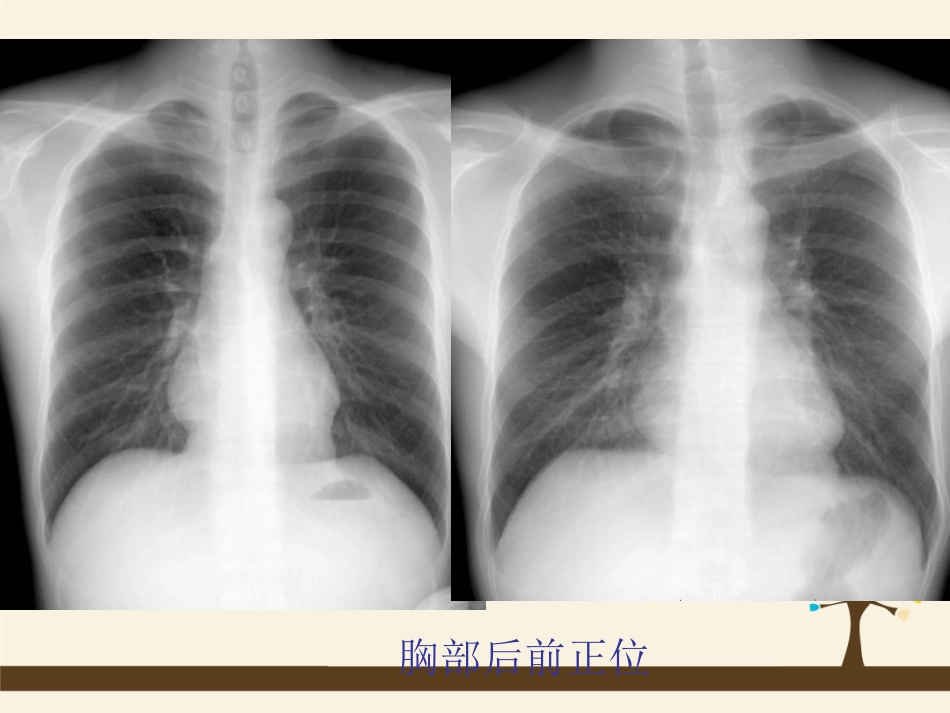

肺——后前立位【摄影体位】病人面向站立于摄影架前。人体正中矢状面与暗盒长轴中线重合,下颌略仰,暗盒上缘超出两肩。双肘屈曲,手背置于臀部,肘部尽量向前贴紧摄影架。【中心线】经肩胛骨下角连线中点(第6胸椎)垂直射人暗盒。深吸气后,屏气曝光。摄影距离为150-180cm。【用途】常规位置。胸部后前正位胸部后前正位肺——仰卧前后位【摄影体位】病人仰卧。人体正中矢状面与暗盒长轴中线重合并垂直,手背放于髂部,肘部弯曲,两肩下垂并内旋,使锁骨放平,以免遮蔽肺尖。肩胛分开,不与肺部重叠。暗盒上缘超出两肩峰3cm。【中心线】同“肺——后前立位”中心线【用途】病人站立困难或病灶靠近背部时,可用此位置。肺部仰卧前后位肺——半卧位前后位【摄影体位】采用常规“肺——仰卧前后位”体位。【中心线】采用常规“肺——仰卧前后位”中心线。【用途】病人立位困难,依靠床后靠垫。肺——侧卧后前位【摄影体位】患者侧卧于摄影台上,暗盒横放竖立,紧靠前胸,暗盒长轴中线与人体正中矢状面重合并垂直,胸部与台面中间可用棉垫垫起,以抬高胸部,使整个胸部能包括在胶片内。【中心线】采用常规“肺——仰卧前后位”中心线。【用途】用于检查少量胸腔积液,空洞的大小,少量气胸或液气胸肺——侧位【摄影体位】患者侧立于摄片架前,被检侧胸部紧靠暗盒。胸部腋中线对准暗盒中线,两臂高举,交叉放于头上,使两肩尽量不与肺野重叠。胸部长袖与暗盒长轴一致,【中心线】经肩胛骨下角,腋中线水平射人暗盒。深吸气后,屏气曝光。【用途】观察肺、纵隔、心脏、胸膜肺部侧位左肺上叶不张左肺上叶不张肺——仰卧侧位【摄影体位】患者仰卧于摄影台上,两臂高举过头,下颌稍抬高,背部可用棉垫垫高。暗盒在患侧胸部旁边竖立,与台面垂直,暗盒长轴与人体腋中线重合并垂直,并与人体正中矢状面平行,上缘约与下颌相齐。上缘包括肋弓。【中心线】同“肺——侧位”中心线【用途】检查胸内液体平面,不能采取站立肺部仰卧侧位肺——前凸位【摄影体位】患者背向摄片架站立,身体正中面或脊柱对暗盒中线。两足分开,使身体站稳。肘部弯曲,手背放于髂部.身体稍离开摄片架约30cm,上胸向后仰,使上背部紧靠暗盒,腹部向前挺出,身体冠状面与胶片成35o角。两肩尽量内旋,使肩胛骨影像不与肺部重叠。暗盒上缘须超出肩部上方约7cm。【中心线】胸骨角与剑突连线的中点,垂直射人暗盒。深吸气后,屏气曝光。【用途】肺尖病变、下胸部叶间胸膜积液及右中叶肺不张等肺部前凸位照片显示:锁骨在胸廓上方,前后肋骨呈水平状影像,肺尖部肺叶清晰。胸部X线摄影的体位选择(1)肋骨结核:常见病,多发于4~7肋软骨部X线摄影难以显示。(2)肋骨骨折:多发于5~8肋,骨折部位不明确时,取全部隔上肋骨的概观像(胸部后前立位)。后肋骨骨折取前后位,腋下肋骨骨折取仰卧正位加滤线栅,呼气位。嘱上肋骨取立位的吸气位,腋中线附近肋骨骨折取切线位。(3)一般常见的肺和支气管病变:取后前立位及侧位。(4)中叶肺不张:取后前位,加前弓位和侧位。(5)下叶不张及盘状肺不张:应透视下旋转体位加照后斜位。(6)胸腔游离积液:取正位,加照患侧侧卧水平正位或斜位。(7)包裹性积液:取正位,加照切线位。(8)肺下积液:取立位、卧位或侧卧水平正位对照。(9)胸膜间皮瘤:取常规正位(10)纵隔气肿:除常规正位外,必须照侧位。(11)纵隔肿瘤:取正侧位。(12)横隔麻痹:取立位的呼气、吸气位对照。(13)隔膨出:取常规正位,必要时行钡餐造影检查。(14)膈下脓肿:除常规正位外,侧位对鉴别诊断很有意义。采用高电压技术,以发现膈下出现的气液面。(15)膈疝:取胃肠造影。腹部X线摄影(一)解剖略!P68(二)摄影前准备同“四肢X线摄影摄影前准备”(三)适应证1.泌尿系统结石。2.腹腔内脏器钙化。3.腹部异物。4.急腹症。5.腹腔内占位性病变。6.消化道穿孔。7.胃肠道梗阻。8.游走肾。(四)禁忌证1.休克病人不宜做立位腹平片。2.非特殊情况下,妊娠3个月内孕妇尽量避免此种检查。(五)X线摄影位置腹部平片——仰卧位(KUB)【摄影体位】病人仰卧于摄影台上,双下肢伸直,人体正中矢状...